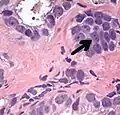

Intraductal carcinoma of the prostate with an infiltrative growth pattern may be morphologically difficult to distinguish from invasive cancer. One focus shows comedonecrosis (arrow), morphologically suggesting Gleason pattern 5 invasive carcinoma (a haematoxylin and eosin, b CK5/6)[20]